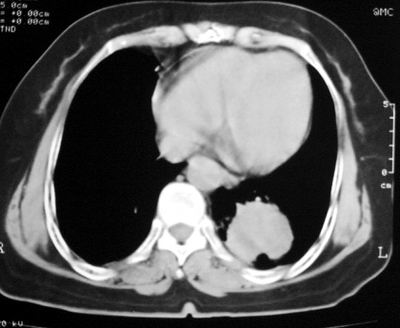

患者,女,64岁,4年前左腮腺"多形性"腺瘤手术治疗史.现复查胸部ct见左下肺块状影,该影与原左腮腺手术是否有联系?

本次复查胸部ct

左下肺癌伴左肺门淋巴结转移

左下肺软组织块影,有分叶、毛刺、空泡及胸膜牵拉征,左下肺周围性肺癌。

支持考虑左下肺原发性肺癌,并左肺门淋巴结肿大

左下周围型肺癌伴左肺门淋巴结及右肺转移可能性大.

左肺下叶周围型肺癌,支持!(软组织肿块+分叶+毛刺+空泡+胸膜凹陷征)

左下肺软组织密度影,可见分叶,边缘可见毛刺征,胸膜增厚,强烈要求左下肺周围型肺癌

左下肺后基底段实性肿块,周围有毛刺,病变周围有肺气肿,与降主动脉间有条带状影相连,病灶4年前查体发现,纵隔内未见肿大淋巴结。考虑.肺隔离症,建议增强扫描与周围型肺癌鉴别。